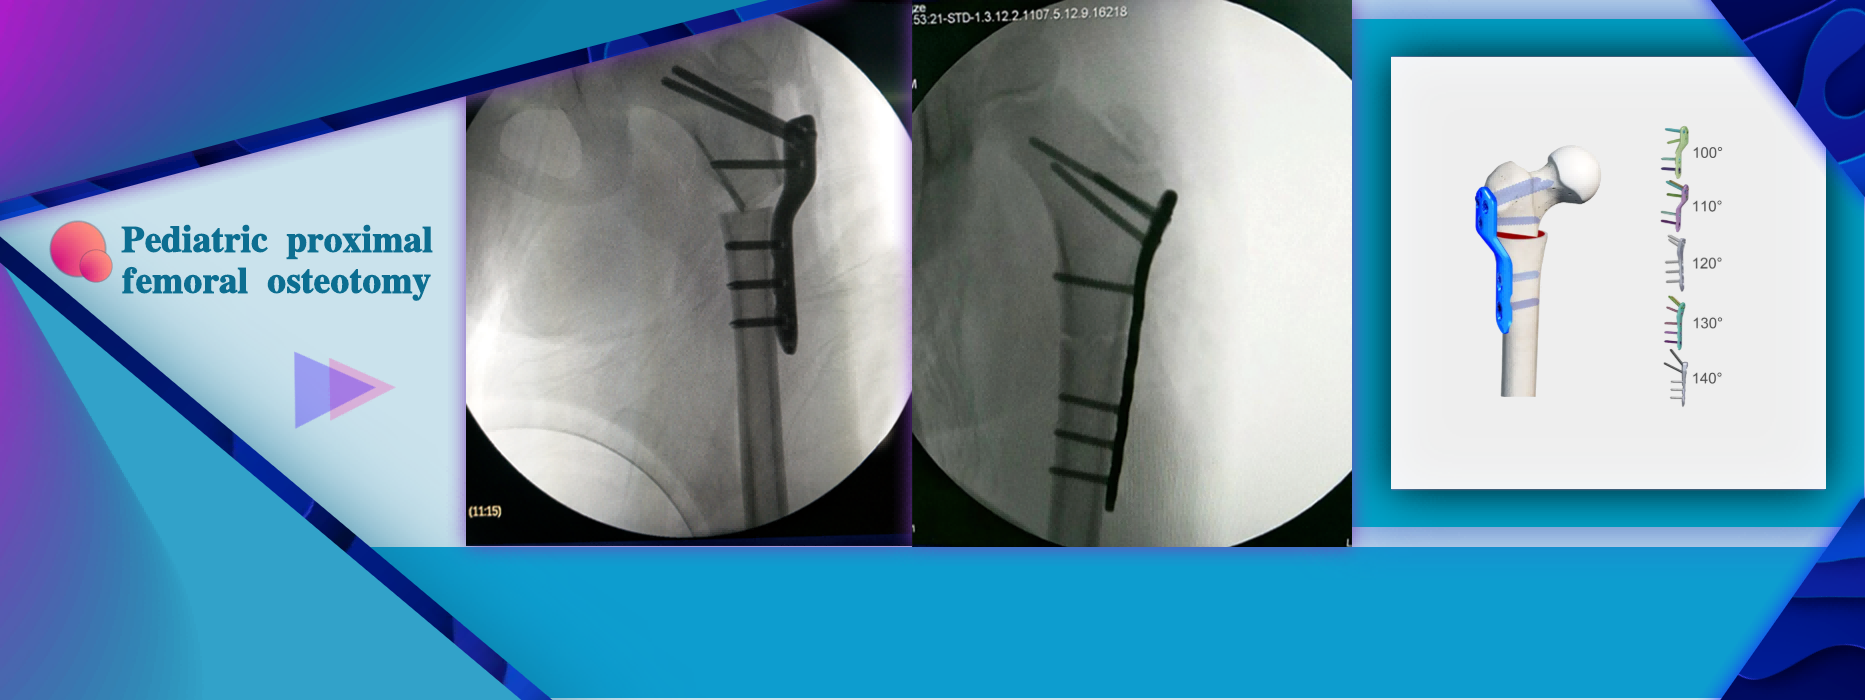

More InformationTreatment for DDH: Proximal Femoral Osteotomy Indication:Inverted, valgus, and rotational osteotomy or fracture fixation of the proximal femur in children

Treatment for DDH: Proximal Femoral Osteotomy Indication:Inverted, valgus, and rotational osteotomy or fracture fixation of the proximal femur in children